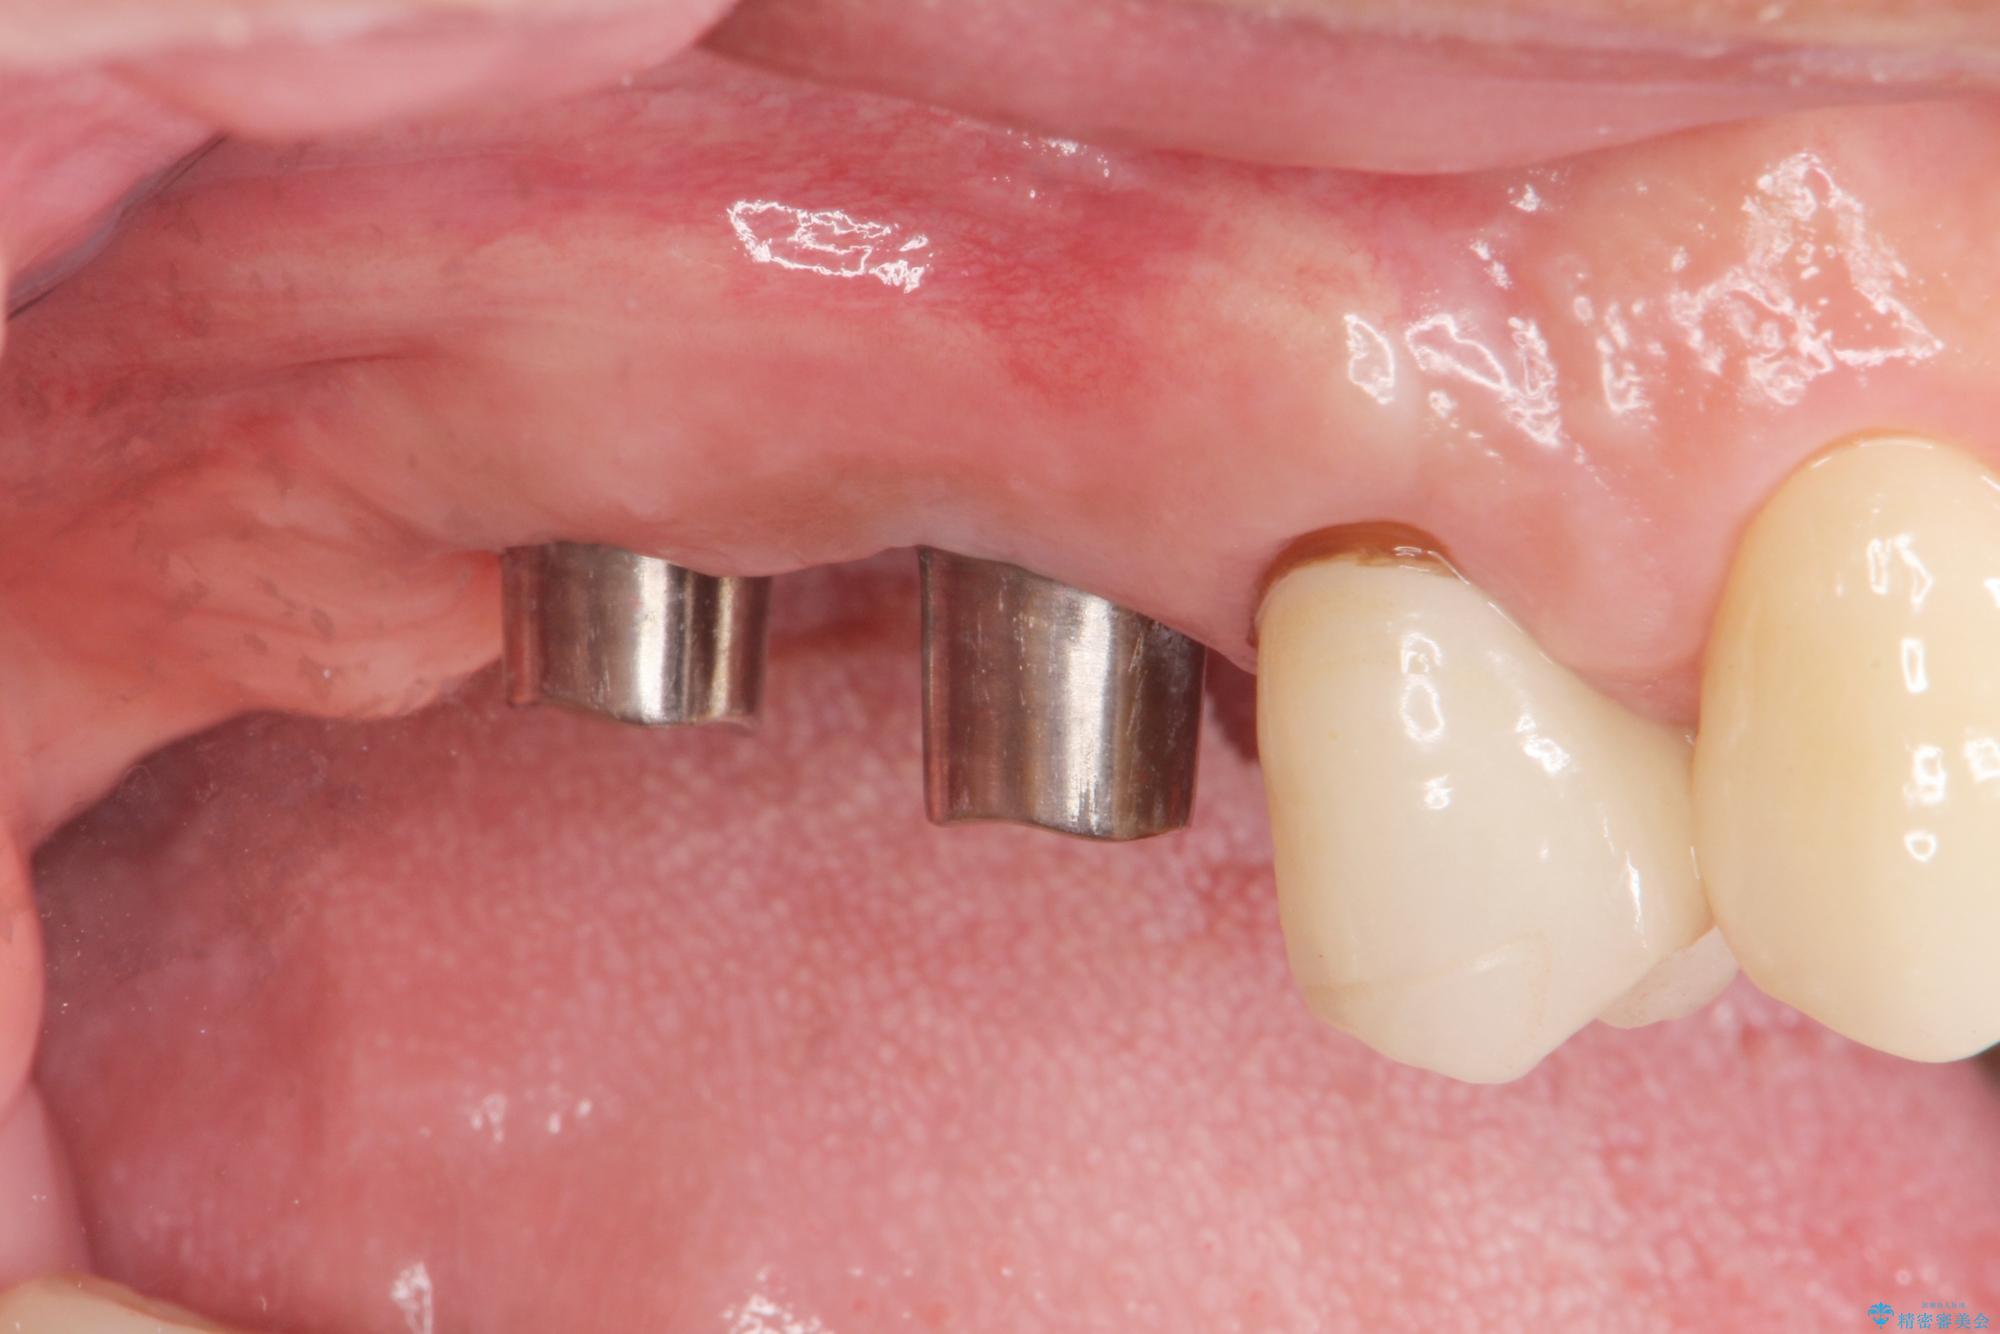

- 歯を抜いたまま放置してしまい、「やはりしっかりと噛めるような状態にしてほしい」とインプラント治療を希望され来院されました。

人工歯根であるインプラントを埋入することで奥歯でまたしっかりと噛める咬合機能を回復します。

- 88万円(インプラント×2・仮歯×2・チタンカスタムアバットメント×2・ジルコニアクラウン×2)費用は治療当時の料金となります

またしっかりと噛めるようになり、食事を楽しめるようになった!と喜んでいただくことができました。